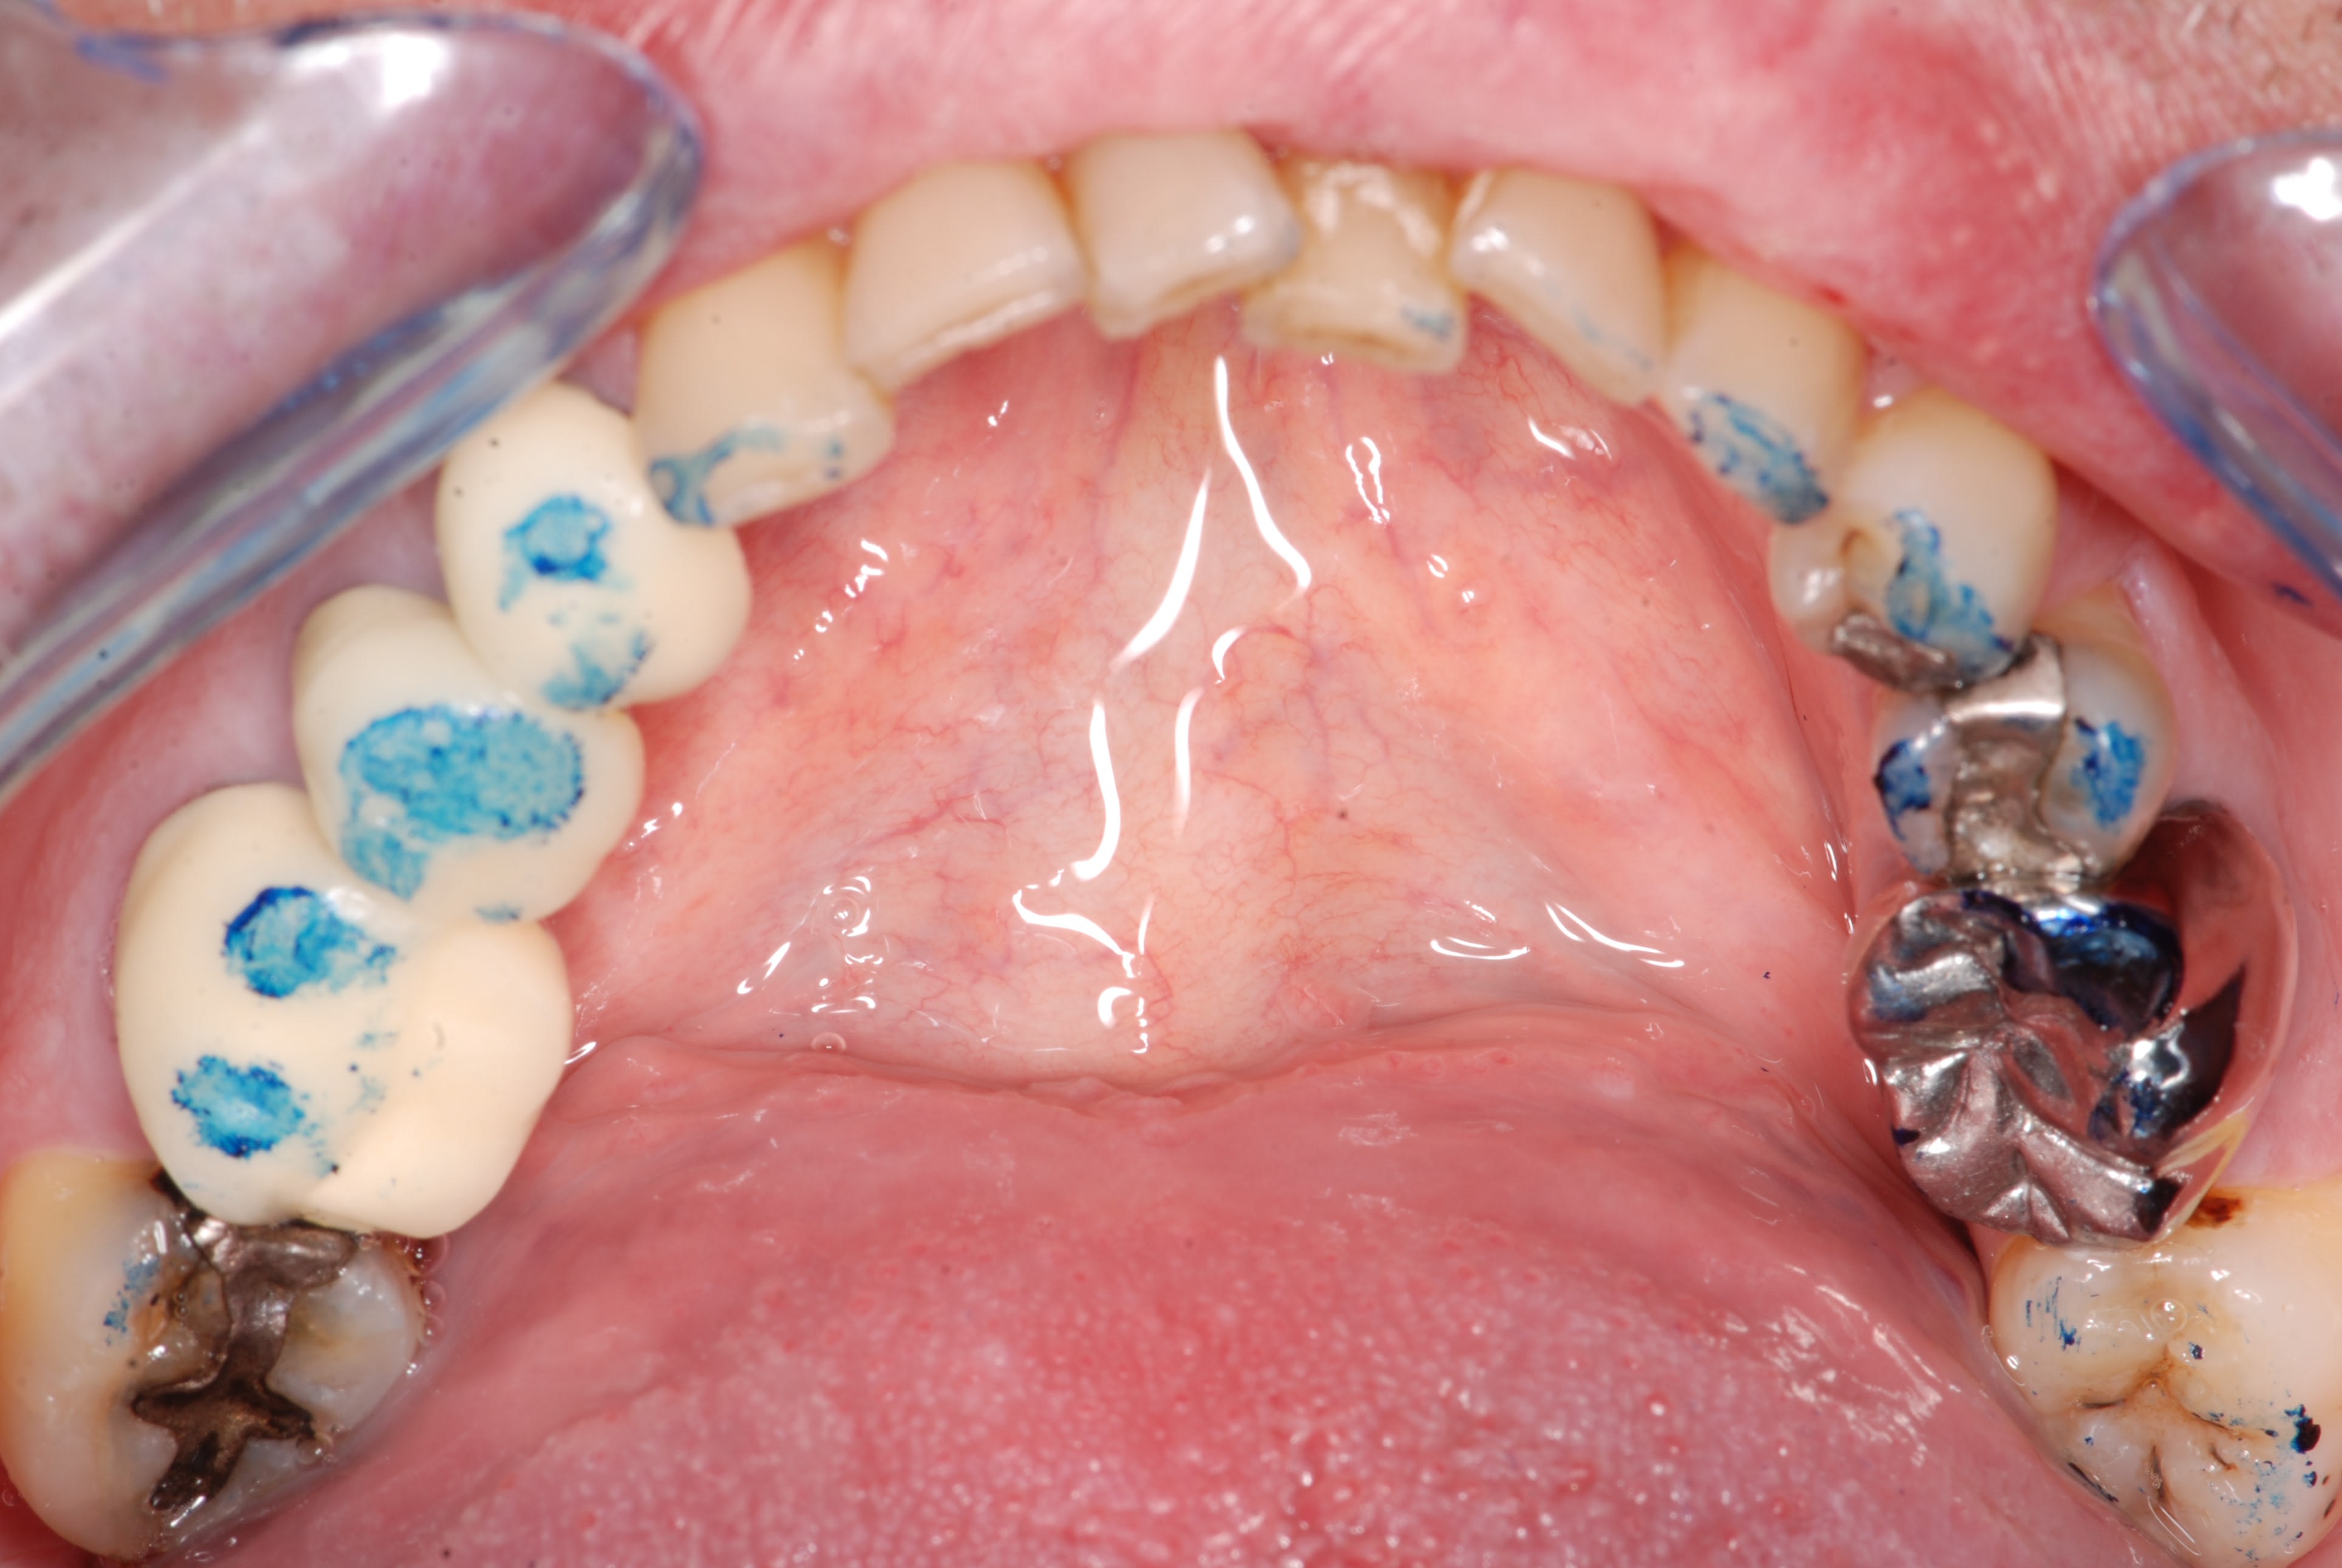

Comme promis, voici les photos du cas.

Comme je disais on dirait que la dent est remontée avec tout son parodonte...

Rien de particulier de noté au cbct fait par mon correspondant implanto. je vais lui demander les coupes

Je t’avoue que je ne m’attendais pas à cet antagoniste. Pas mal, ta colle!

Repartons dans les conjectures, alors.

Je pense à une 16 bloquée dans son éruption (celles ci sont souvent cariées et par « contagion » provoquent des caries radiculaires sur leurs voisines, d’où, extraction de 5 et 7.

Ça expliquerait la position de cette dent, mais pas cette couronne en inocclusion. Là, tout ce que j’imagine, c’est que la couronne a été faite alors que 5 et 7 étaient absentes par un prothésiste qui a cru corriger une erreur d’empreinte et un dentiste qui s’en cognait....